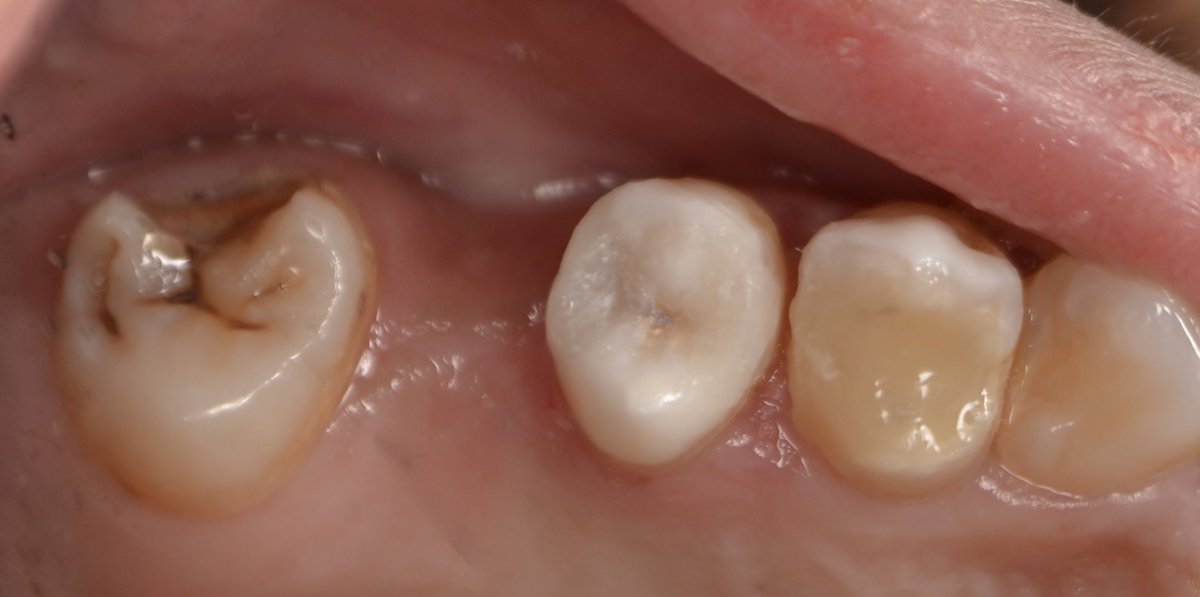

Successfully completed endodontic treatment on #36 with Radix Entomolaris, a challenging and rewarding case ✨

Grateful to have performed it under the supervision of @DrKhawlahSays and @HananShu

Thank you for your guidance and continuous support in advancing our clinical skills.